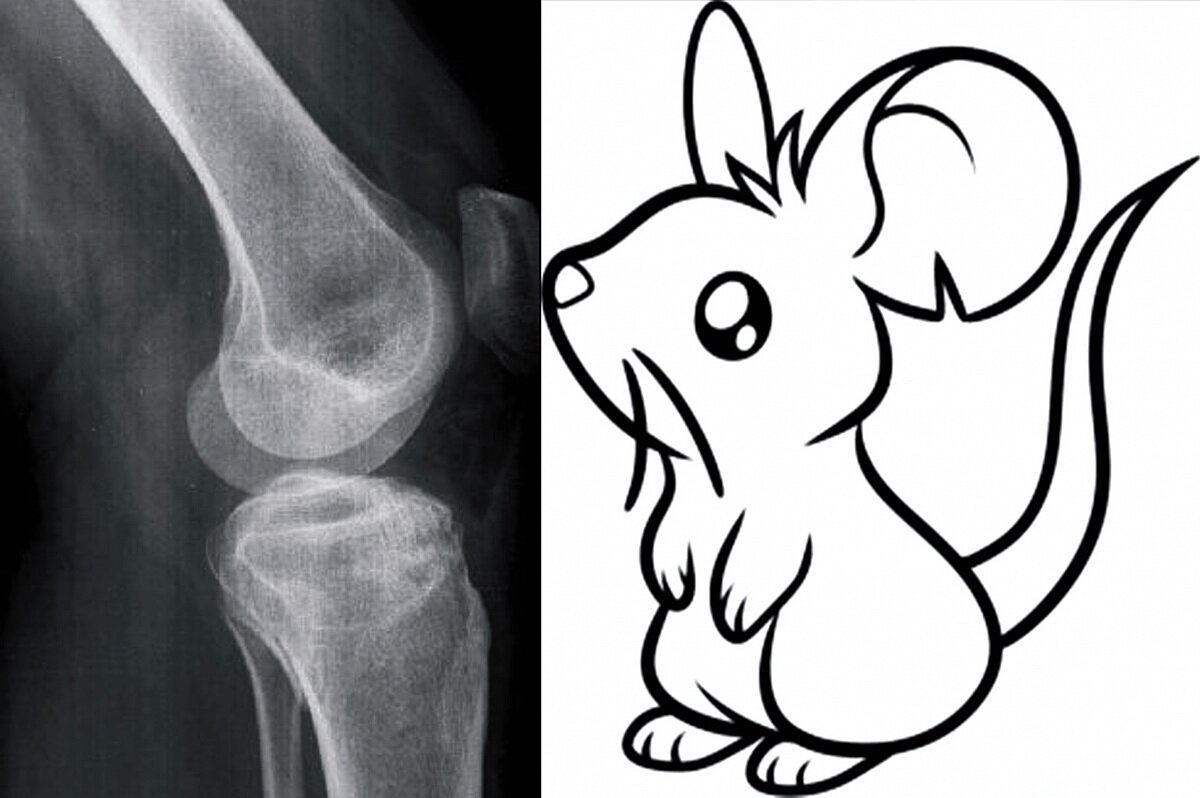

Что за зверь такой – «mus articularis»?

Когда пациент на приеме у врача жалуется на то, что в суставе при ходьбе «что-то бегает», первая мысль в голове доктора – вероятно свободное внутрисуставное тело, именуемое в обывательском кругу «суставной мышью». «Суставная мышь» или свободное внутрисуставное тело в своем подавляющем большинстве случаев является результатом ранее перенесенной травмы сустава, о которой пациент давно забыл и связать эти два обстоятельства ему, больному, зачастую бывает не просто. Некоторым все-таки удается вспомнить, что «когда-то давно» был хороший удар в область сустава или подворот ноги с «хрустом» и последующей болью. Почему не обратился к врачу? «Я думал ушиб», «болело не долго и все прошло»… Вот за такими, безобидными на первый взгляд, фразами могут скрываться проблемы недалекого будущего в жизни практический каждого из нас.

По своей структуре «свободное внутрисуставное тело» состоит из хрящевой, костной тканями или их комбинации. В редких случаях могут быть иные виды соединительной ткани. Как правило, образуется в момент травмы сустава – хрящевые или костно-хрящевые внутрисуставные переломы. Очень часто не диагностируются своевременно. Это может быть часть поврежденного мениска, фрагмент краевого перелома надколенника или мыщелков бедренной и большеберцовой костей. Чем дольше в полости сустава находится свободное тело, тем более сглаженными становятся его края, грани. Неприятность «суставной мыши» заключается не только в том, что её наличие может быть источником боли в суставе, но и в том, что она часто приводит к прогрессирующему разрушению суставного хряща. Деформирующий артроз сустава в таких случаях протекает особенно неблагоприятно.

В ходе комплексного обследования пациента, обратившегося за медицинской помощью, есть ряд методов и исследований, которые могут выявить или обнаружить свободное тело в полости сустава. Как правило, начинается обследование с выяснения жалоб и истории развития заболевания, далее следует осмотр области суставе в статике и динамике, его внешний вид; по необходимости могут назначаться определенные анализы и лучевые методы исследования. Последние как раз и являются наиболее вероятными способами обнаружения патологии сустава. Рентгенография в стандартных проекциях, ультрасонография (УЗИ), КТ, МРТ…